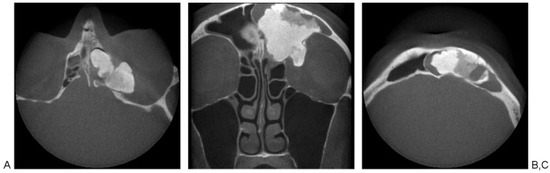

Open Surgical Management of an Asymptomatic Giant Frontal Sinus Osteoma

:Case Report